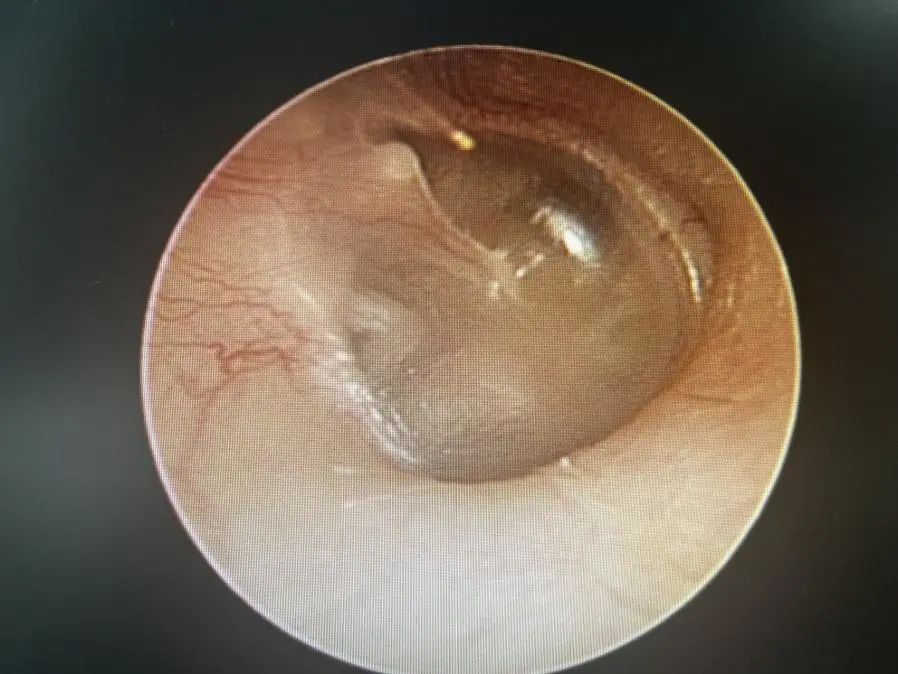

正常鼓膜

醫(yī)生在視頻耳內(nèi)鏡下發(fā)現(xiàn)左側(cè)鼓膜有一個(gè)破口,有血跡殘留在鼓膜上,還做了純音聽(tīng)閾檢測(cè),檢查結(jié)果顯示,小花的左耳聽(tīng)力呈中度傳導(dǎo)性耳聾。